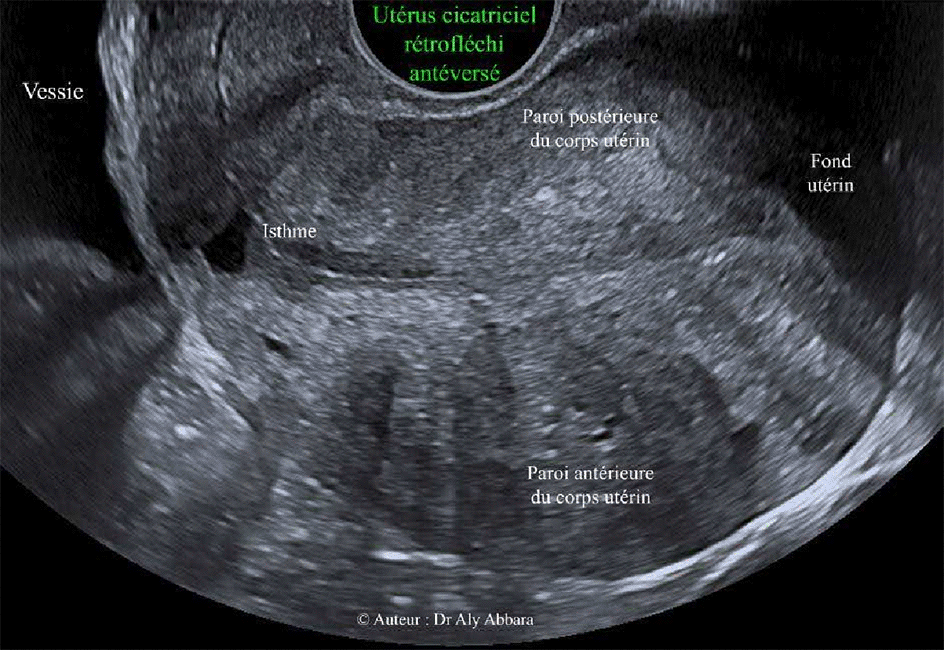

Images échographiques animées montrant un utérus rétroversé antéfléchi

cicatriciel avec une béance de la partie intérieure de l'ancienne cicatrice d'une césarienne segmentaire transversale (isthmocèle) |